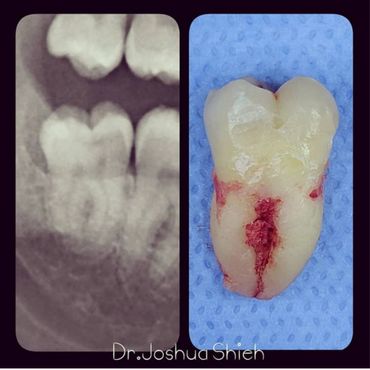

If the tooth is planned for extraction, an x-ray of the area will be taken to plan for the type of extraction.

A surgical extraction is a more complex procedure. It is used if a tooth may have broken off at the gum line or has not come into the mouth yet. Surgical extractions are commonly performed by general dentists or oral surgeons depending on the case. Sometimes it’s necessary to remove some of the bone around the tooth or to cut the tooth in half in order to extract it. For surgical extractions, patients receive local anesthetic. A suture is usually required to control bleeding and facilitate healing.

Wisdom teeth are the third set of human molars. Unfortunately, in some cases, those teeth are impacted fully or partially in bone or soft tissue and cannot erupt causing pain, discomfort and swelling. Additionally, most people have difficulty accessing these teeth during brushing or flossing causing accelerated decay and gum problems. Wisdom teeth have also been notorious for causing crowding, improper bites and pressure when they start erupting. The arrival of these late-breaking teeth can cause trouble as they are often impacted (trapped in the jawbone) because there is not enough room for them in the mouth. Our jaws are a lot smaller than those of our early human ancestors, who needed bigger jaws and more teeth for the type of food they chewed. In most people, wisdom teeth can do more harm than good and we often recommend their removal.

It can take a long time for wisdom teeth to erupt and you may not even notice the harmful effects in your mouth until you experience sudden and severe discomfort. Cramped for room, impacted wisdom teeth grow out at odd angles or remain trapped below the gums. Adjacent teeth can become prone to decay because of the unfavourable position of the wisdom teeth.